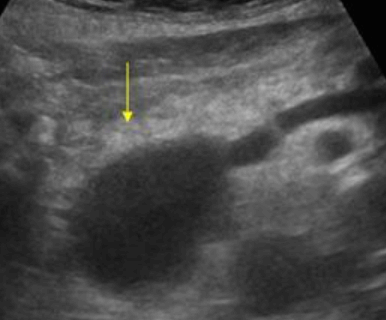

Choledocholithiasis US finding

- 총담관 내에 후방음향음영을 동반한 강한 에코가 관찰된다.

- 총담관의 확장 소견이 보인다. ( 7mm 이상)

- 담석이 관찰되지 않고 간외, 간내담관의 확장소견을 시사하는 엽총징후(shotgun sign)이나 평행관 징후(parallel channel sign)가 관찰되기도 한다.

- 엽총징후(shotgun sign): 간외 담관이 확장되어 간외 담관과 문맥이 이웃해 관찰된다.

- 평행관 징후(parallel channel sign): 간내 담관이 확장되어 인접하고 있는 문맥과 나란히 2개의 관상구조로 나타난다.